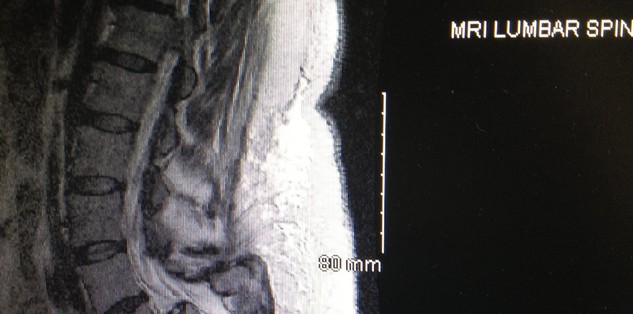

I had back pain for quite awhile. At first it was manageable, but it gradually got worse. I had gone from having to sit down frequently while shopping to using a walker and eventually to using a motorized scooter to even go to the grocery store. Someone suggested that I see what the doctors had to say at Rothman. I made an appointment at the King Of Prussia location. The doctor there managed to get me an appointment for an MRI for which my PC had not been able to do. I was called shortly after the results and told I should see Dr. Rihn in Media on August 15th. On August 28th I was scheduled for surgery to correct my spine I had a severe slip. Dr. Rihn was an excellent surgeon and made sure I knew exactly what was going to happen and what it all entailed.